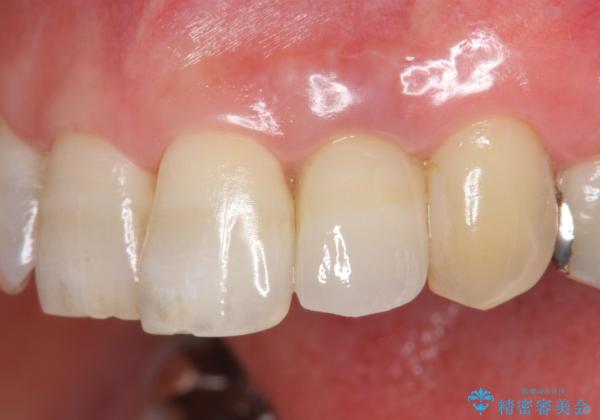

維持を保つためのファイバーコア築盛を行い、精密なジルコニアクラウン製作を行います。

自然な色調のクラウンが製作され、審美障害が改善し喜んでいただくことができました。